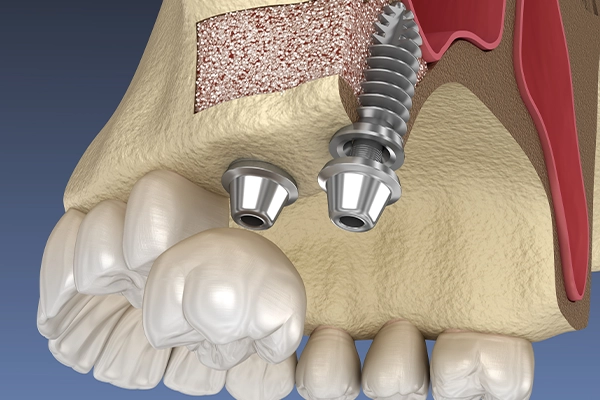

インプラント埋入

左上1番は抜歯後、抜歯即時は非適応なためリッジプリザベーション(※1)を行い待時埋入を行いました。

リッジプリザベーションの様子

(※1)リッジプリザベーションとは

歯を抜くと、支えていた周囲の骨は役目を終えたと感じて自然に痩せていってしまいます。これを防ぐための処置がリッジプリザベーションです。

抜歯した直後の穴に「骨を補う材料」を詰め、骨の吸収を最小限に抑えます。あらかじめ骨のボリュームを維持しておくことで、その後のインプラント治療をより安全・確実に、かつ見た目も美しく仕上げることが可能になります。

リッジプリザベーション後、骨が十分に成熟したため待時埋入を行いました。

埋入時の様子